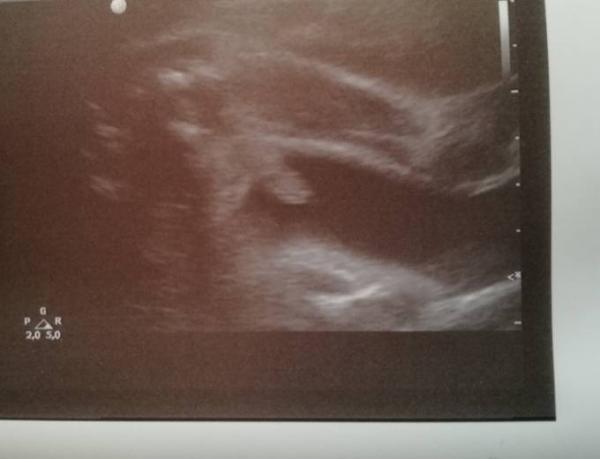

Danach ging es zum Baby TV und meine mum hoffte das der Zwerg nun endlich zeigt was es wird. Was soll ich sagen, innerhalb von 4 Wochen ist von nichts zu sehen ein eindeutiger schnippel gewachsen.

Im Anhang das US Bild auf dem es deutlich zu sehen ist was es wird